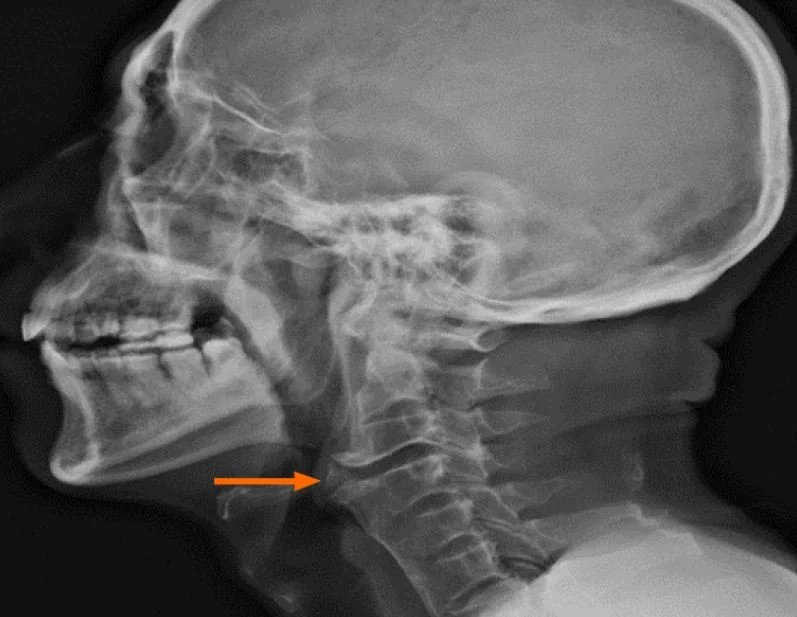

A 69 y.o. male presents with difficulty swallowing.

Our patient had ankylosing spondylitis with an anterior osteophyte in the cervical spine causing dysphagia.  Ankylosing spondylitis is a seronegative autoimmune arthritis characterized by osteophyte formation, enthesitis and sacroliitis.  Peripheral arthritis pericarditis, and pulmonary fibrosis may occur also occur.   Classically,  bamboo spine develops with vertebral body fusion from syndesmophytes between ossified intervertebral discs.

Our patient had his osteophyte surgically removed.  His ankylosing spondylitis was treated with a JAK inhibitor.